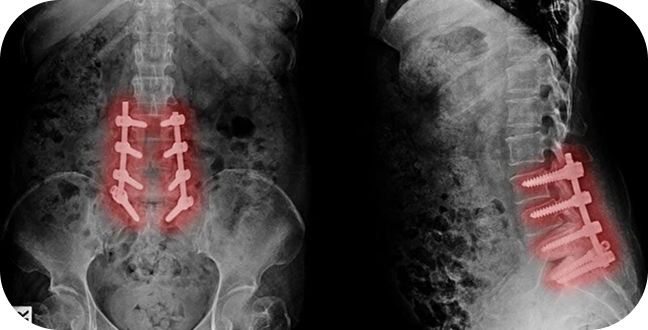

Spinal Cord Stimulation (SCS) is an advanced, implantable treatment for chronic pain that does not respond to conventional therapies.

A small device — similar to a pacemaker — sends mild electrical impulses to the spinal cord, disrupting pain signals before they reach the brain.

If the trial is successful, a small generator is placed under the skin, usually under local anesthesia.